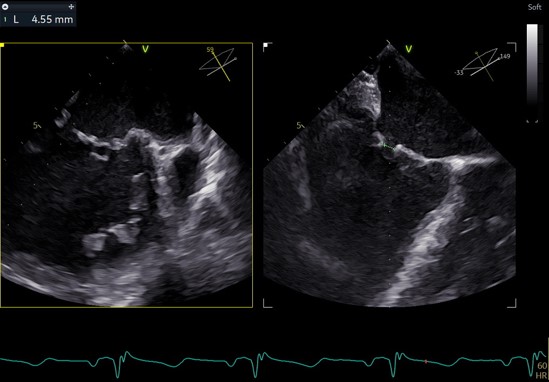

③ 二尖瓣前叶(A1)长度28.5mm,二尖瓣后叶(P1)长度: 10.4mm;二尖瓣前叶(A2)长度28.4mm,二尖瓣后叶(P2)长度: 12.7mm二尖瓣前叶(A3)长度22.6mm,二尖瓣后叶(P3)长度: 11.5mm;

④ 3区前后叶对合gap 4.5mm,2区前后叶对合gap 3mm。

3区gap

穿刺高度

3D复测穿刺高度